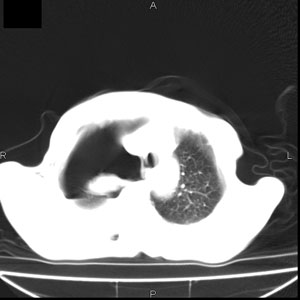

患者男,77岁,于3日前从树上摔下,头部查ct示蛛血,硬膜下出血,上腹部ct未见明显异常,右侧胸腔积液,左侧如常。肺部拍片示右侧肋骨多发骨折住院后今日来查肺部ct,我看到的是1。右侧胸腔血气胸并右肺上叶,中叶压缩性肺不张,2。右肺下叶肺挫伤并多发肋骨骨折,肌内及皮下积气3。左侧少量胸腔积液,我想请教的是3天前左侧胸腔里没有积液今天怎么出现了呢,是什么原因呢?请讨论。

回复楼主   左侧液气胸,液体来源1、肯定有血液成分,多少不一定。2、胸膜腔渗液,由于肺压缩、活动度下降,肯定胸膜吸收有问题,导致积液增多。

因为3天前病人刚摔的时候,左侧胸腔受伤不严重,故而当时没有胸腔积液,但病人受到这么大的伤害,胸膜腔内的液体动态平衡肯定会受到影响,所以过一段时间后才出现胸腔积液。